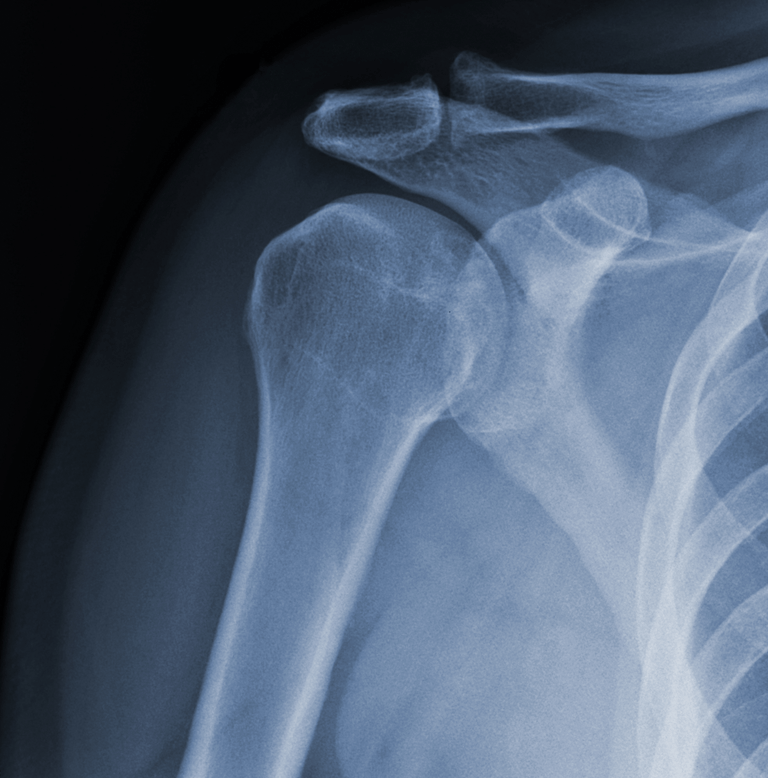

Evaluamos y tratamos lesiones que afectan los huesos, músculos, ligamentos y tendones. Desde fracturas y luxaciones hasta lesiones de tejidos blandos, ofrecemos un manejo médico y quirúrgico adecuado para una recuperación óptima.

Cirugías Ortopédicas Avanzadas.

Realizamos procedimientos quirúrgicos especializados, como:

Artroscopia: Técnica mínimamente invasiva utilizada para diagnosticar y tratar lesiones articulares, como desgarros de meniscos, lesiones de ligamentos y problemas en el cartílago.

Reemplazos articulares (prótesis de cadera, rodilla y hombro).